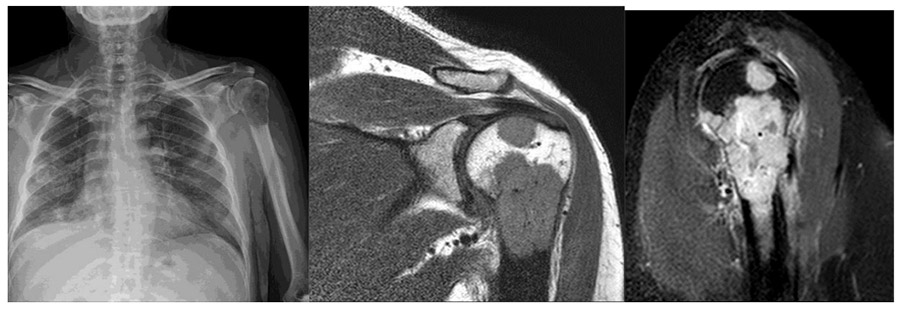

CASE 2: Kidney (renal cell) cancer metastasizes to the humerus bone.

Before the surgery: The X-ray shows bone destruction at the superior end of the humerus, and the MRI shows the tumor extending outside the bone.